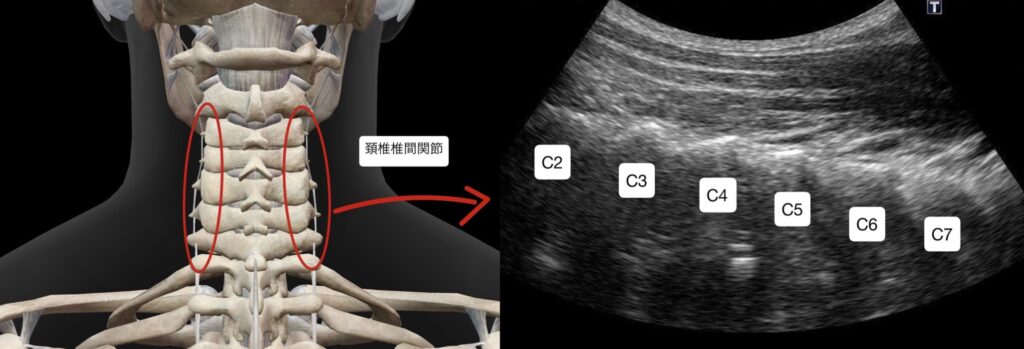

・超音波エコーガイド下での圧痛所見(指で押して痛みが出る所見)では、肩甲骨内側部分にある肩甲挙筋ファシア重責部と肩甲背神経周囲の圧痛と頸椎5/6番の椎間関節周囲に痛み程ではないが違和感がある。

・頸椎5/6番の椎間関節周囲の脊髄神経後枝内側枝に対し鍼通電を行った

・初回の施術から1週間弱空けての来院だったが、肩甲骨内側の安静時での痛みが消失した。動作での痛みが残り、首の違和感が鈍痛に変わってきたとのこともあり頸椎椎間関節の脊髄神経後枝内側枝に対し施術を行ったところ動作痛も消失した。